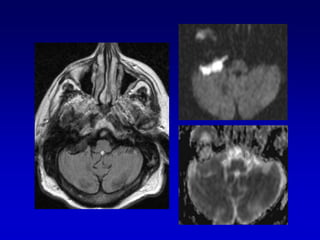

GLOMUS YUGULAR(paraganglioma)Erosion de la espina yugularInvasion hacia la caja timpánica

Caso 2TAC-RM

Caso 3TAC RM ANGIO

Caso 3

postembolizacion

Glomus timpánico